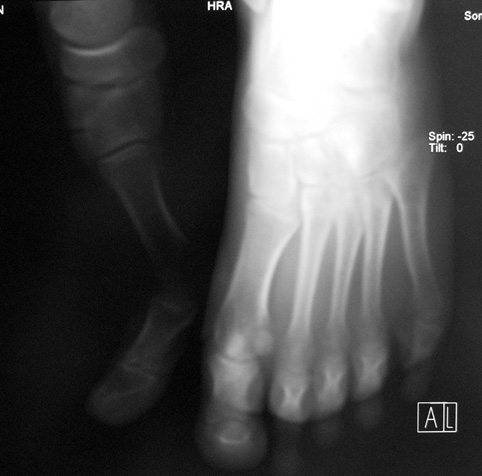

El parmağı (metakarp) ve ayak parmağı (metatars) kısalıkları doğuştan tek başına, geniş bir sendrom grubuyla birlikte, travma sonrası, Freiberg hastalığı (avasküler nekroz) sonrası görülebilir.

Doğuştan metakarp ve metatars kısalığının görülme sıklığı 1/1000’den azdır. Kadınlarda erkeklere göre 5 kat daha fazla görülür ve sıklıkla (%72) iki taraflıdır. En sık 4. parmak tutulur. Bu tür olgularda sorunun nedeni tam olarak bilinmemekle brlikte deformitenin genellikle epifiz plağının erken kapanmasından kaynaklandığı düşünülmektedir.

Metakarp kısalığında kozmetik görünümün bozulması ve dominant elin kullanımı sırasında yorulma, metatars kısalığında ise kozmetik haricinde metatarsalji, kısa parmağın dorsale kayması sonucu deformite oluşması, plantar yönde açılanması sonucu ağrı ve bası ülserleri, ve ayakkabı giymede zorluk nedeniyle ameliyat gerekebilir.

Doğuştan metakarp ve metatars kısalıklarının redavisi için pek çok teknik tanımlanmakla birlikte en çok akut uzatma sonrası kemik uçlarına greft konması ve distraksiyon osteogenezi (kallotasis) kullanılmaktadır. 1 cm.den daha fazla uzatma gereken olgularda kallotasis yöntemi önerilmektedir. Kliniğimizde de metatars ve metakarp uzatma için unilateral eksternal fiksatör ve sirküler eksternal fiksatör yardımıyla distraksiyon osteogenezi yöntemi tercih edilmektedir.